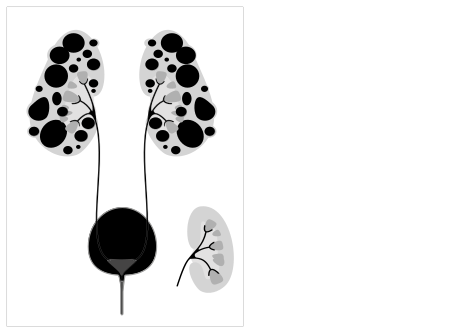

Cystic kidney disease refers to a wide range of hereditary, developmental, and acquired conditions[1] and with the inclusion of neoplasms with cystic changes, over 40 classifications and subtypes have been identified. Depending on the disease classification, the presentation may be at birth, or much later into adult life. Cystic disease may involve one or both kidneys and may, or may not, occur in the presence of other anomalies.[1] A higher incidence is found in males and prevalence increases with age. Renal cysts have been reported in more than 50% of patients over the age of 50.[2] Typically, cysts grow up to 2.88 mm annually and may cause related pain and/or hemorrhage.[2]

Of the cystic kidney diseases, the most common is polycystic kidney disease with two sub-types: the less prevalent autosomal recessive and more prevalent autosomal dominant.[1] Autosomal recessive polycystic kidney disease (ARPKD) is primarily diagnosed in infants and young children while autosomal dominant polycystic kidney disease (ADPKD) is most often diagnosed in adulthood.[1]

Cystic kidney disease includes various conditions related to the formation of cysts in one or both kidneys. The most common subset is polycystic kidney disease (PKD) which is a genetic anomaly with two subsets, autosomal recessive polycystic kidney disease (ARPKD) and autosomal dominant polycystic kidney disease (ADPKD). Consequently, causation can be genetic, developmental, or associated with systemic disease which can be acquired or malignant. Examples of acquired cystic kidney disease include simple cysts and medullary sponge kidney (MSK). Other types of genetic cystic kidney disease include juvenile nephronophthisis (JNPHP), medullary cystic kidney disease (MCKD), and glomerulocystic kidney disease (GCKD).[citation needed]

PKD causes numerous cysts to grow in the kidneys. These cysts are filled with fluid and if they grow excessively will lead to kidney damage. Mutations in genes PKD1 and PKD2 are responsible for autosomal dominant polycystic kidney disease (ADPKD). Those genes encode for polycystic proteins and mutations regarding those genes are inherited and responsible for the disorder of autosomal dominant cystic kidney disease. In the United States, more than half a million people have PKD, making it the fourth leading cause of kidney failure. PKD affects all races and genders equally and those with PKD have a possibility of developing cysts in other organs such as liver, pancreas, spleen, ovaries, and large bowel. Usually, these latter cysts do not impose a problem. Half of patients have no manifestation of symptoms, but symptoms may include: hematuria, back or abdominal pain, or the development of hypertension. The disease is usually manifested before age 30, and 45% develop kidney failure by age 60. Mutation in the HDK1 gene is currently thought to be responsible for autosomal recessive polycystic kidney disease (ARPKD), often diagnosed shortly after birth and usually before 15 years of age.[citation needed]